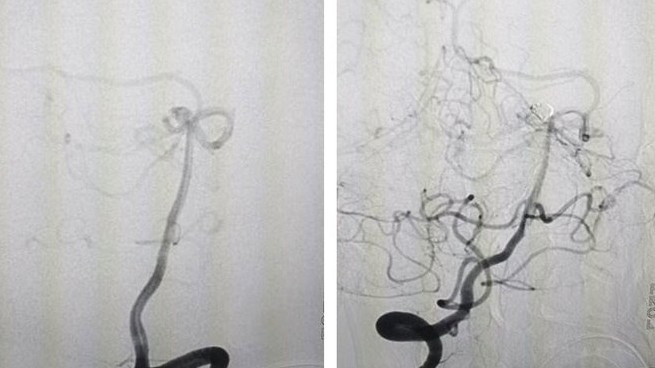

Nhanh chóng hôn mê do vỡ túi phình mạch não

Thời sự xã hội -  09/04/2021

Kíp cấp cứu Trung tâm y tế Huyện Yên Lập, tỉnh Phú Thọ, chụp cắt lớp vi tính sọ não, chẩn đoán ban đầu xuất huyết não. Ngay lập tức, bệnh nhân được đặ...